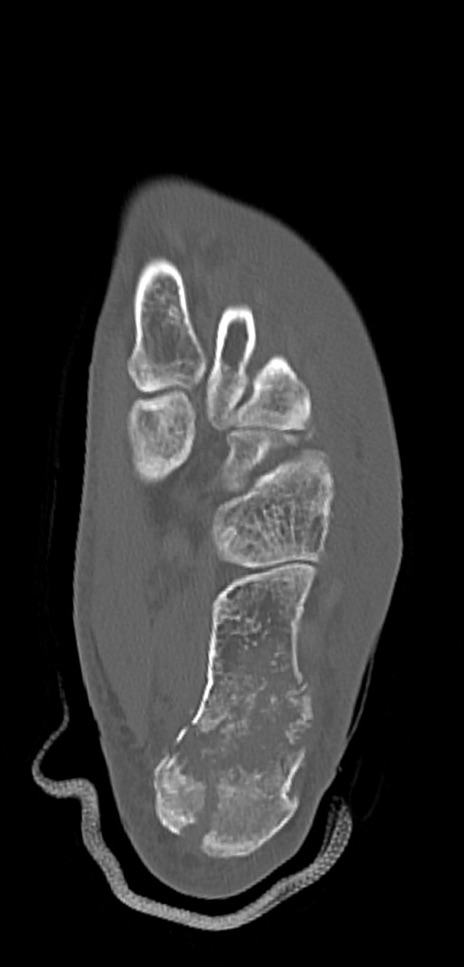

冠状断像

矢状断像